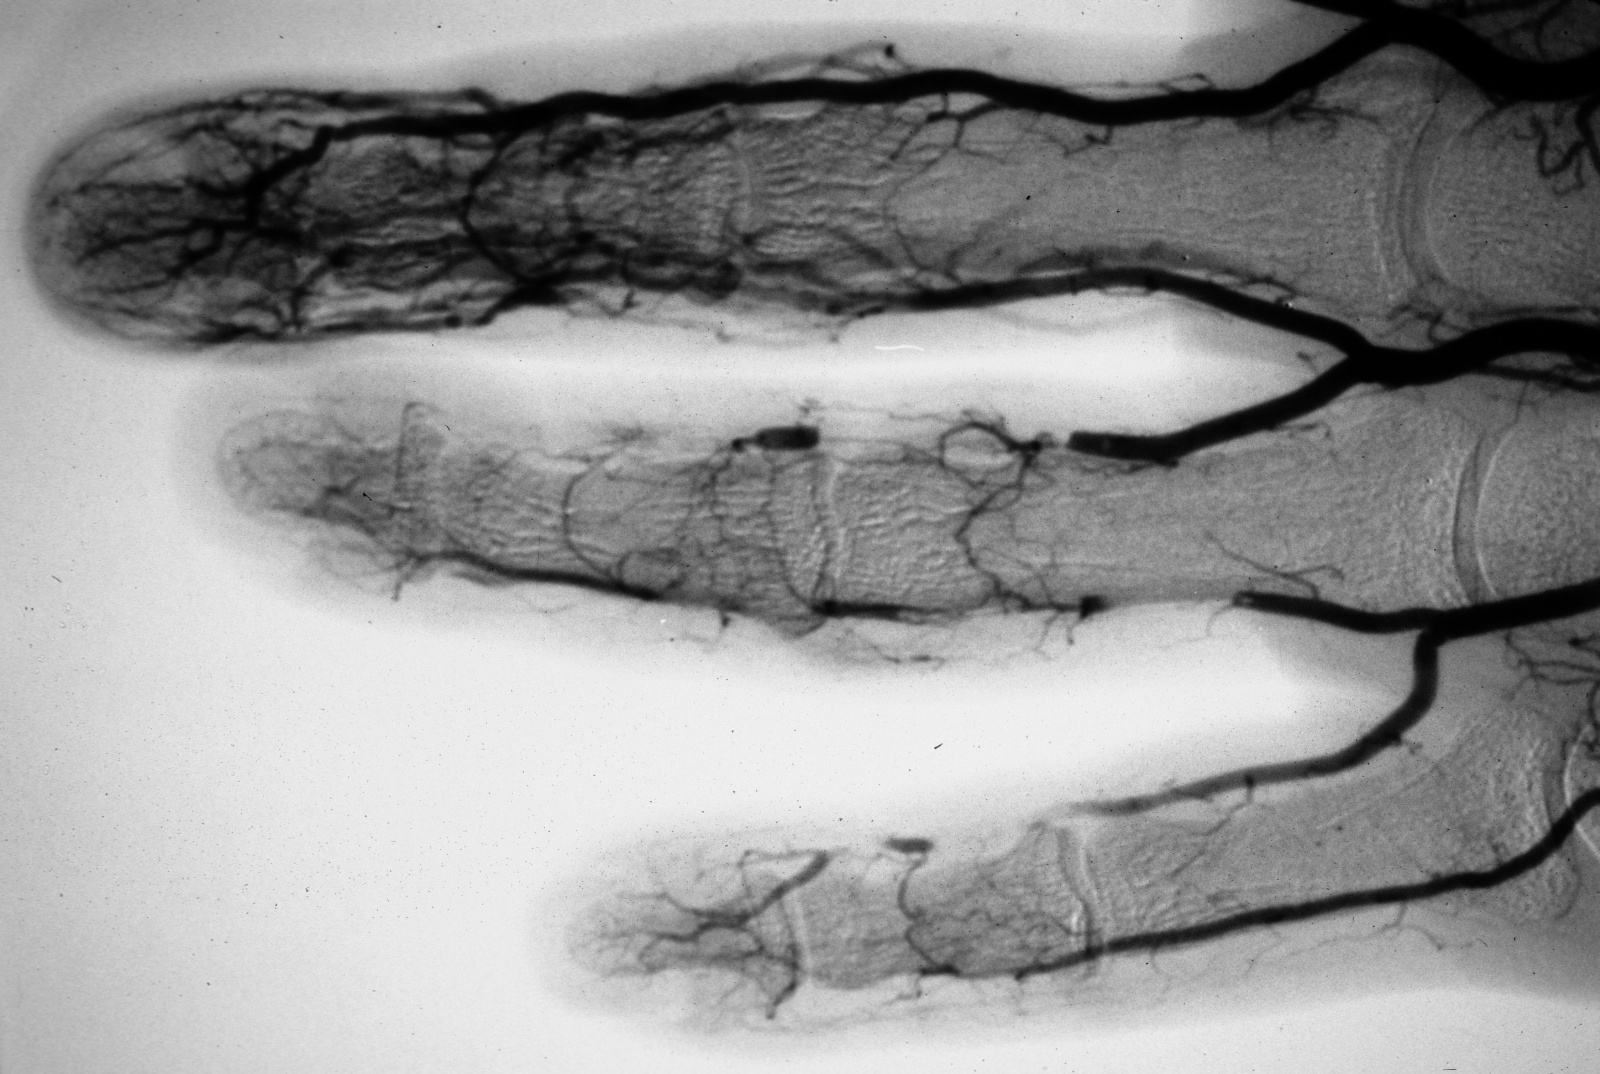

An arteriogram demonstrated partial blockage of the ulnar artery in the palm consistent with a partially occluded ulnar artery aneurism.

It also showed segmental digital artery occlusion suggestive of tiny emboli in the middle, ring and small fingers.